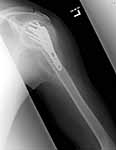

Attached are pics of malunion w/ osteotomy and fixation w/ Norian in gap after improving valgus impaction.

Xrays look better. We will see if he improves as well.